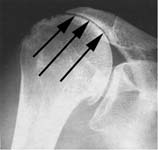

Rotator cuff tear arthropathy (or shoulder arthritis with a large rotator cuff tear) is diagnosed by a history of progressive loss of shoulder function usually without an injury along with a physical examination showing weakness and grinding on movement and a typical appearance on X-ray. In these films the humeral head can be seen contacting the undersurface of the coracoacromial arch (indicated by the arrows in Fig. 12). The most important test for cuff tear arthropathy is the x-ray characteristically showing rounding off of the humeral head as it contacts with the undersurface of the coracoacromial arch. [See Fig. 13).